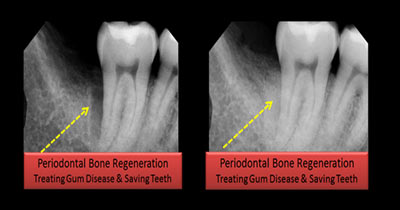

Dr. PRASHANTHY.R.BDS, MDS, FICOI,DICOIPeriodontist / Implantologist-Board certified Diplomate (ICOI )Healthy Gums and Teeth for a Beautiful Smile

Specialist inPeriodontist